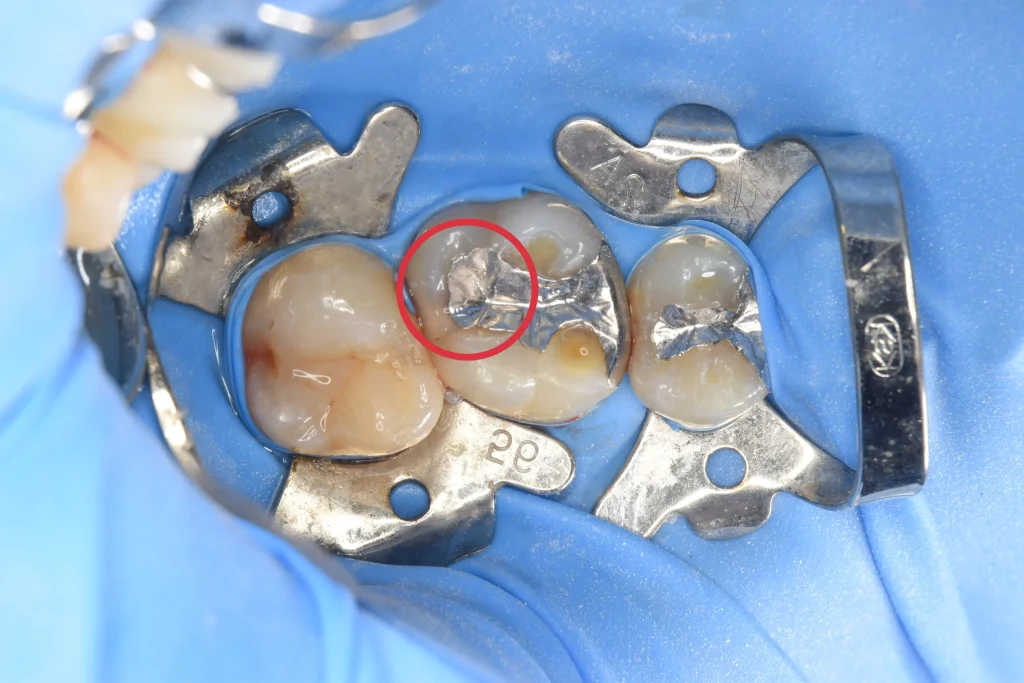

赤丸が虫歯のある場所です。